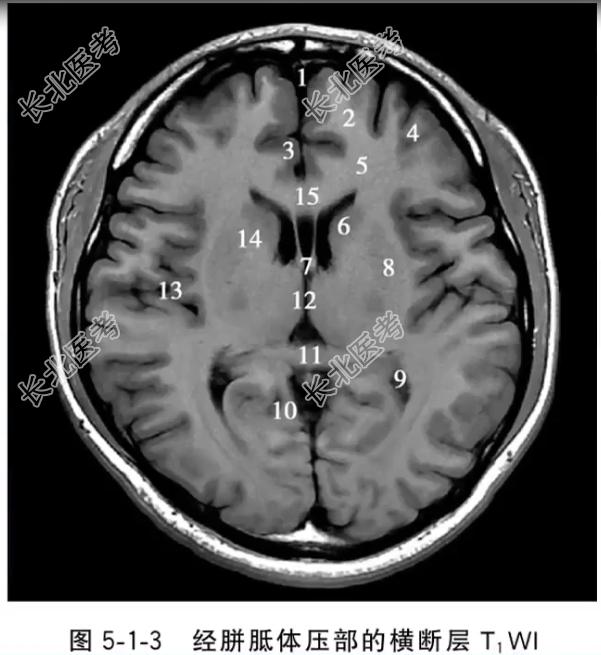

- 单项选择题经胼胝体压部的横断层T1WI中,标记为8的结构是

A、尾状核头

B、豆状核

C、侧脑室三角区和脉络从

D、扣带回峡

E、内囊前肢